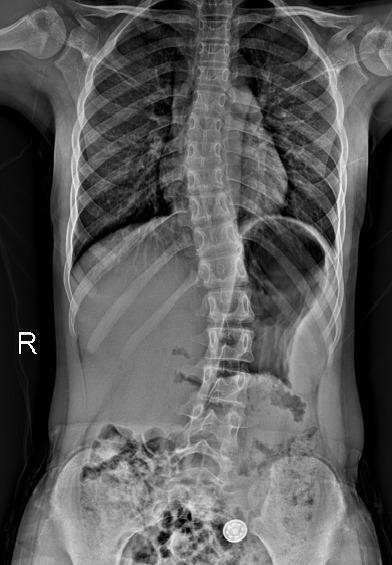

一年前,小圆父母察觉到孩子异常——耸肩驼背、双肩与腰部明显不对称。最初以为是学业负担重所致,但症状持续未见好转。今年4月,家人带她前往常德市第一中医医院求诊。检查结果令人揪心:脊柱全长片清晰显示其胸椎向右弯、腰椎向左弯,形成典型“S”形,胸椎4-10节及胸11至腰4节Cobb角分别达14°与25°,脊柱柔韧性为75%。

令人欣喜的是,在门诊完成10次PSSE训练并坚持居家锻炼后,小圆3个月后复查显示疗效显著——胸椎Cobb角降至6°,腰段Cobb角大幅收窄至15%,侧弯外观明显改善。